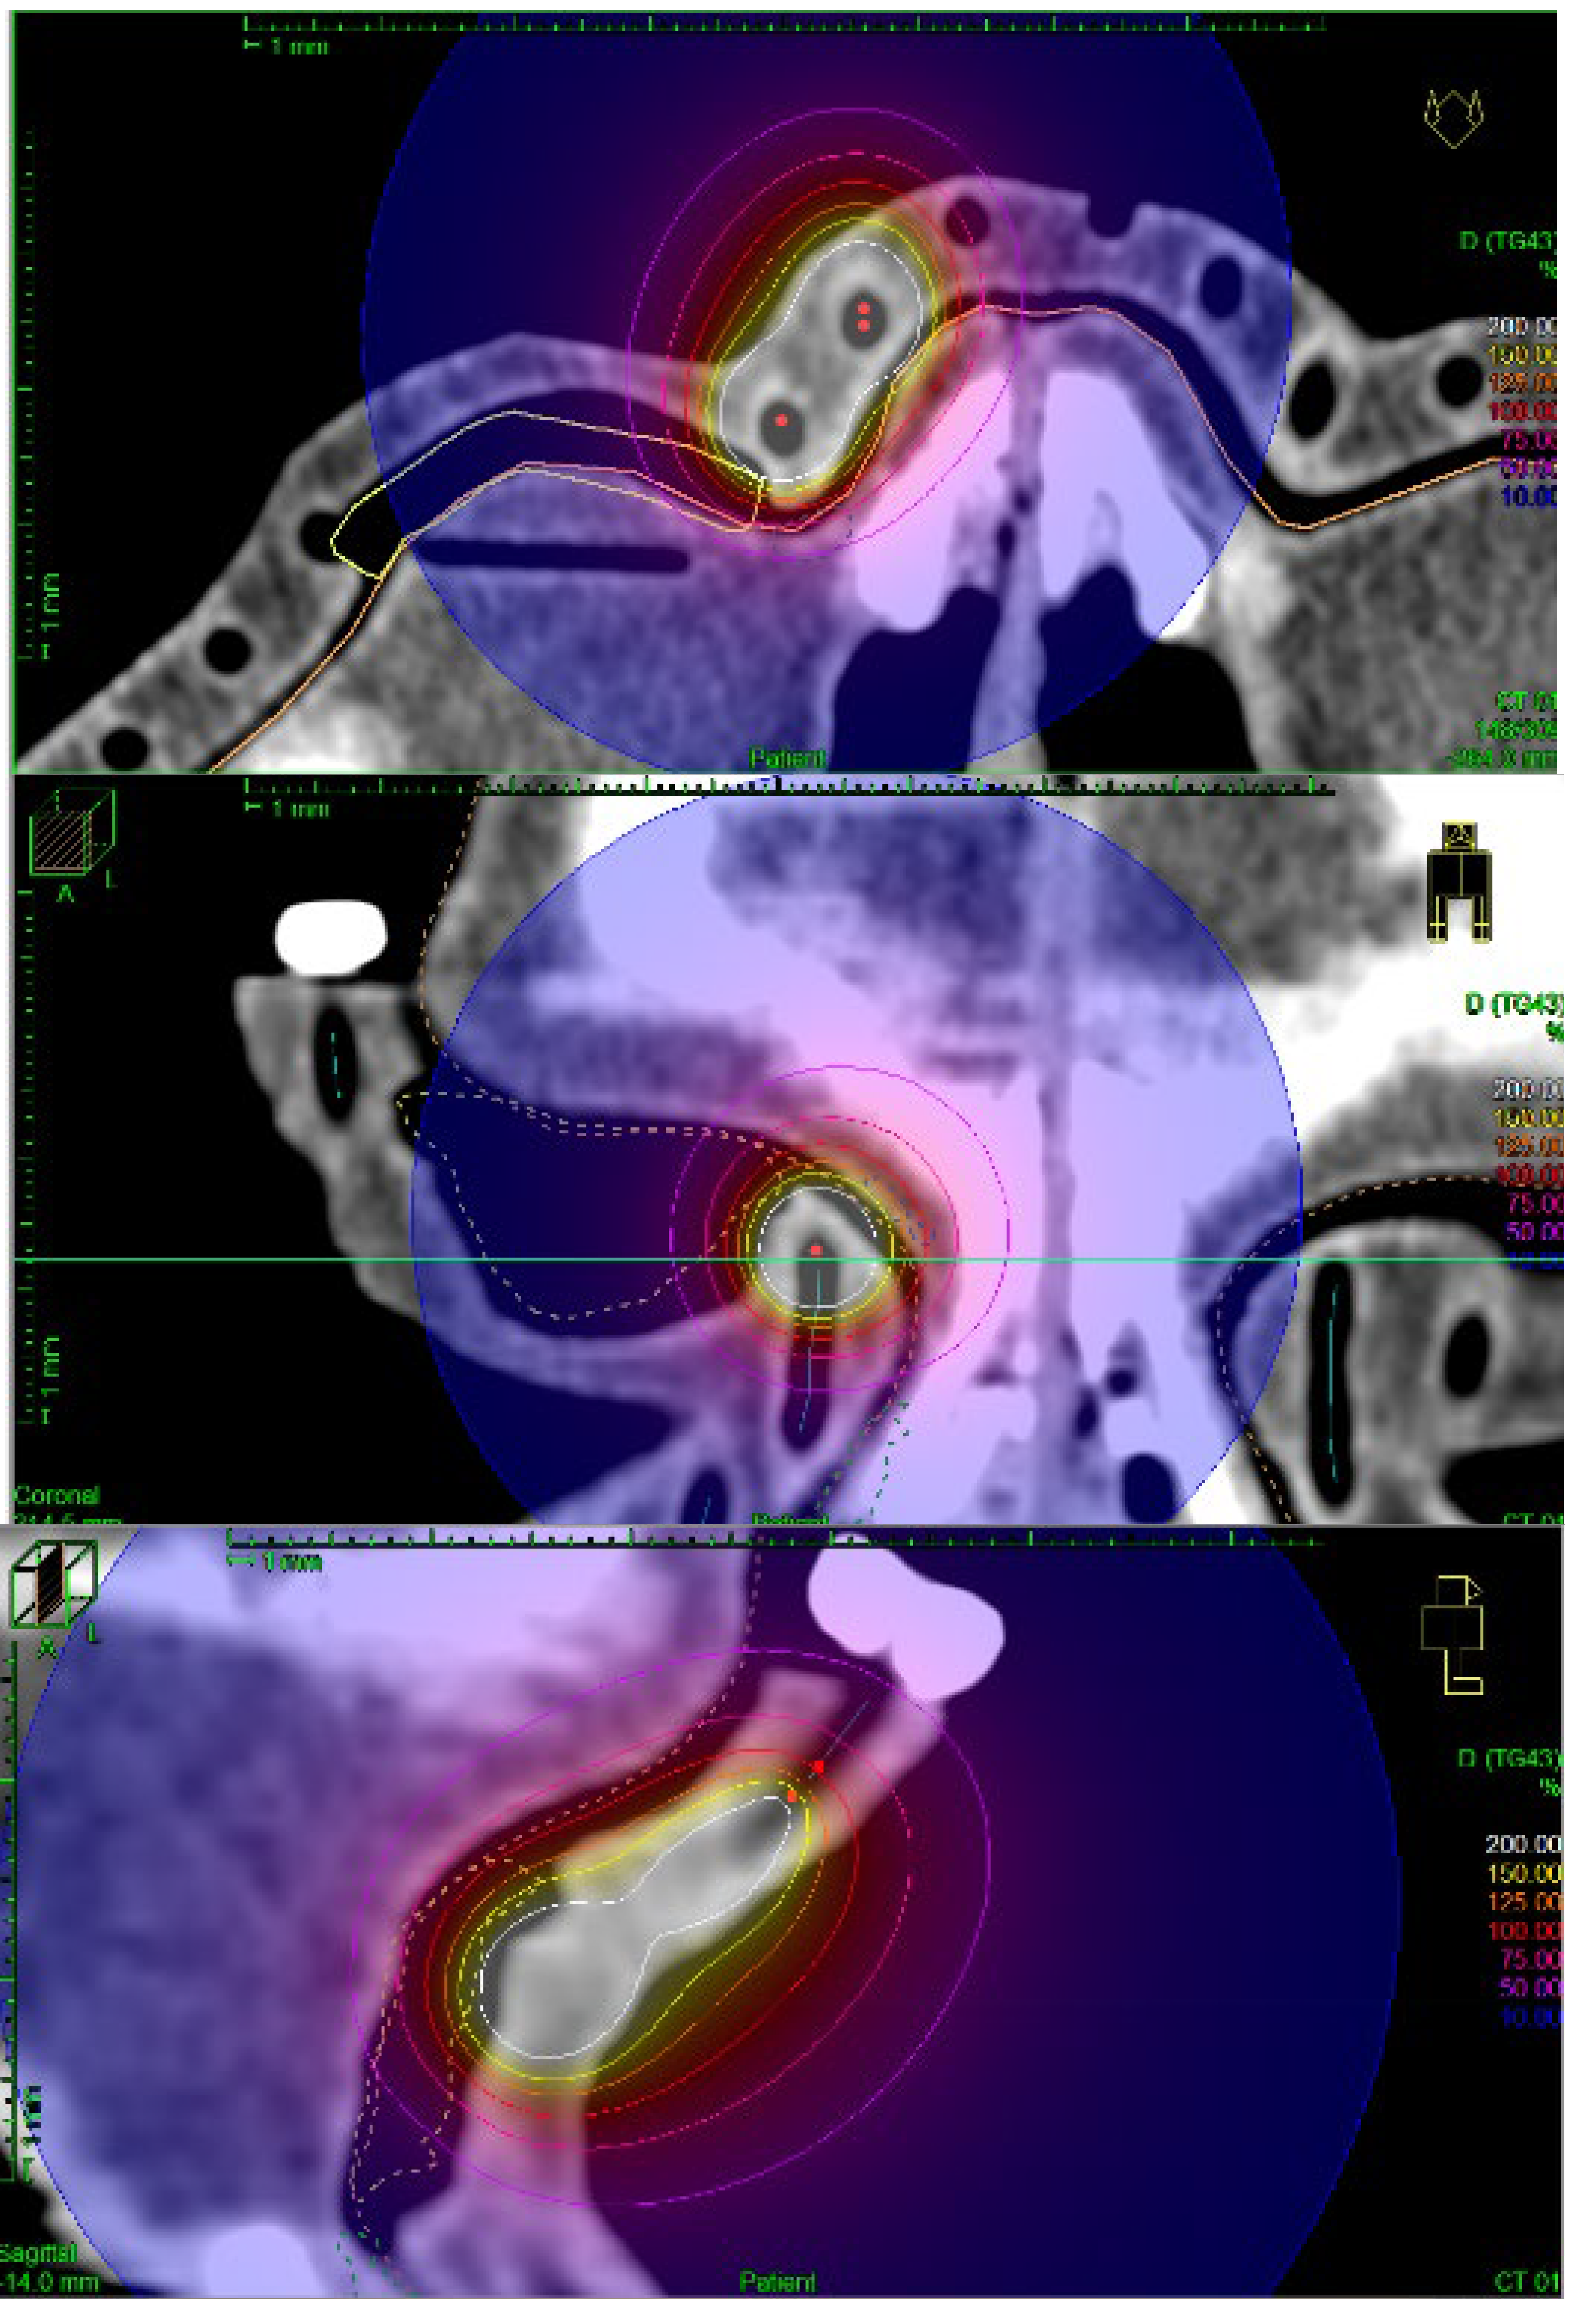

The treatment planning process was based on determining the dose prescription points (patient points) in the TPS at the border of the target areas. It was possible to perform preliminary normalization and optimization of the plan on the designated points. To improve the automatically generated plan, manual normalization, and graphical optimization processes were performed, which improved the dose distribution near the target volumes. The prescribed dose in each plan was 10 Gy. The step distance between each source stop position was set as 1 mm. Each treatment plan was recalculated in several ways. First, the TG-43 formalism, which is recommended for use in brachytherapy planning procedures, was used. TG-186 formalism was used as a second, which took into account the presence of lead shielding and the scattering resulting from the use of a PLA applicator. The TG-186 formalism was used in two ways in standard (TG186) and high accuracy (TG186H) modes. An example of the obtained isodose distribution for the treatment plan realized by the authors is shown in Figure 7 and Figure 8.

Figure 7. Sample dose distribution obtained during the treatment planning process with clearly visible channels for brachytherapy catheters inside a 3D printed surface applicator.

Figure 8. Detailed view of sample isodoses obtained during the treatment planning process; the optimization of the treatment plans.